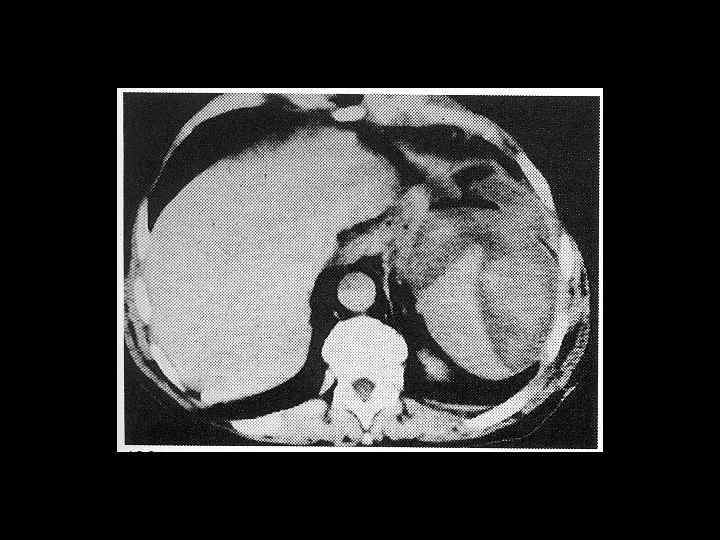

АКТУАЛЬНЫЕ ВОПРОСЫ РЕНТГЕНОЛОГИИ ЛУЧЕВАЯ ДИАГНОСТИКА ЗАБОЛЕВАНИЙ СЕЛЕЗЕНКИ Кисты и абсцессы селезенки

АКТУАЛЬНЫЕ ВОПРОСЫ РЕНТГЕНОЛОГИИ ЛУЧЕВАЯ ДИАГНОСТИКА ЗАБОЛЕВАНИЙ СЕЛЕЗЕНКИ Травма и инфаркт селезенки